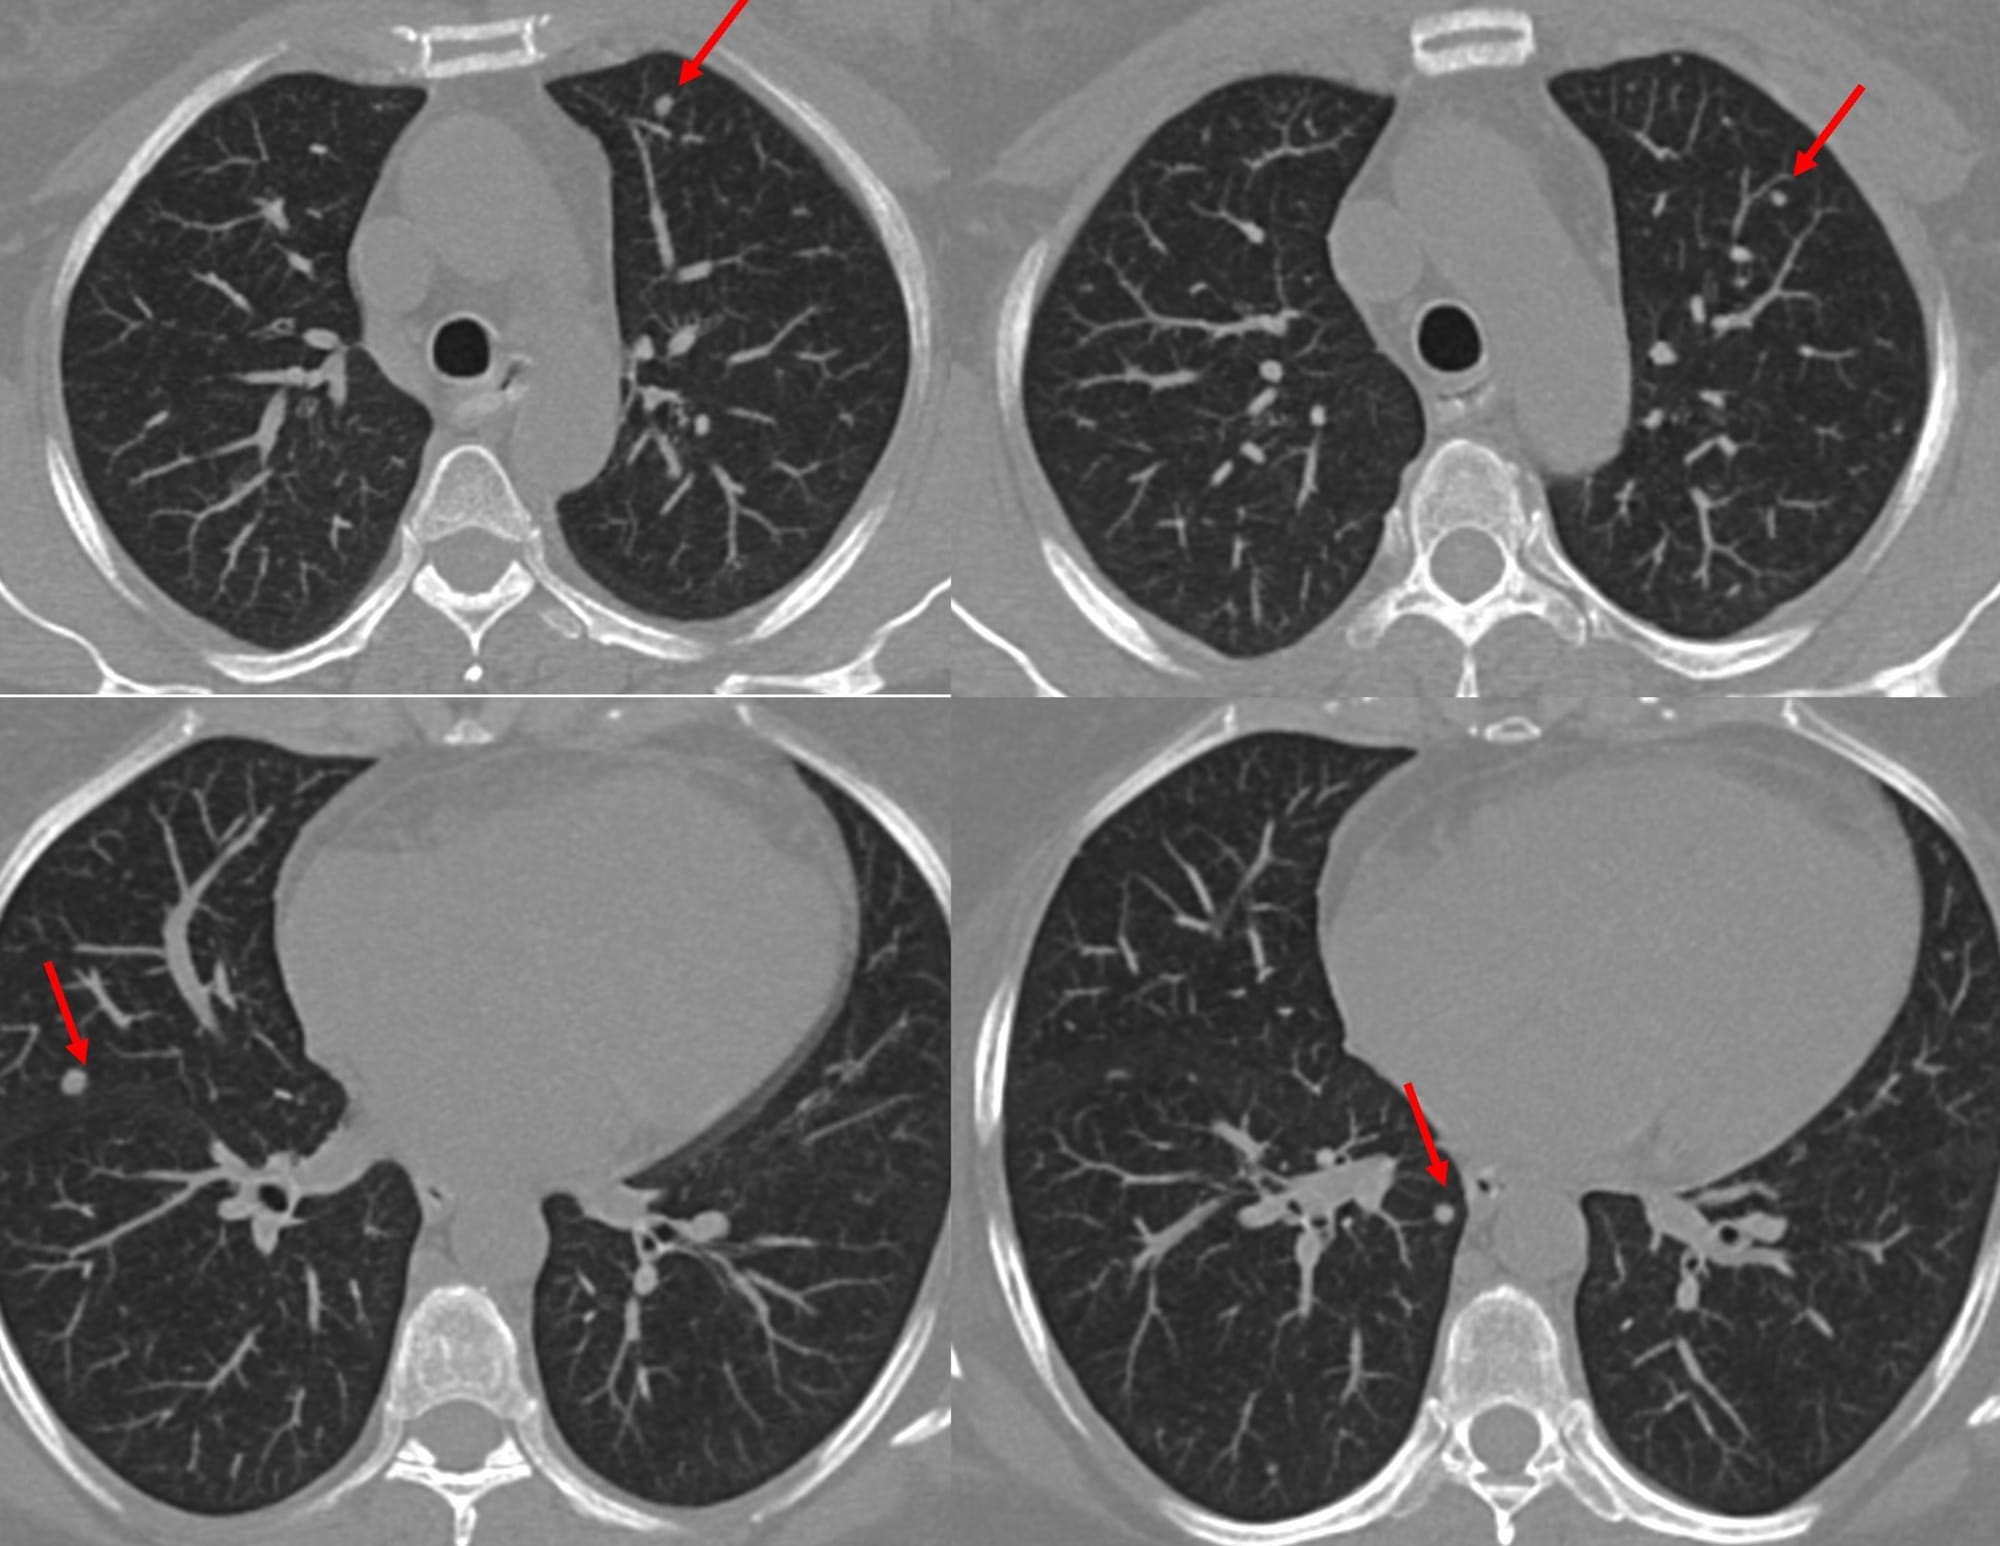

A 55-years old, recently diagnosed to have carcinoma breast, was found to have multiple < 5 mm sized lung nodules on a staging PET/CT.

She was referred for a CT guided biopsy. The left lower lobe nodule seemed to be the simplest to approach in the prone position.